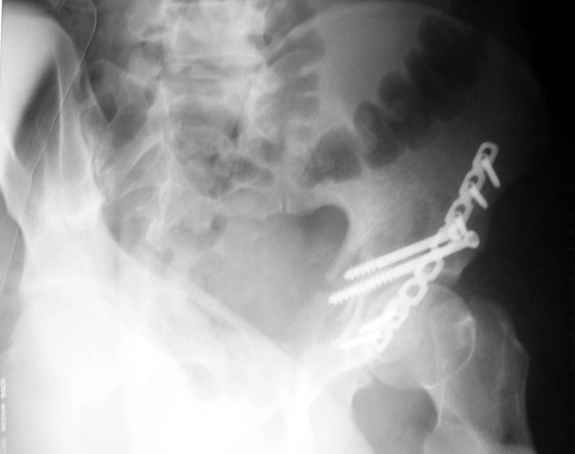

Высылаю пример еще одного случая, остеосинтез пластиной из подвздошного доступа.

Анатолий, во второй презентации, какой Ваш диагноз, не поперечный ли перелом ацетабулум? Вы написали, Ваш доступ был подвздошный, по моему мнению, ваш доступ лимитировал Вас к anterior column и постоянно надо было держать в контроле за натяжением femoral artery and vein, иначе грозит закупоркой артерии или вены, (были и такие experience), при сгибании в тазобедренном суставе, которое ухудшает и так ухудшенный доступ. По-моему, если доступ расширить, т.е. formal Ilioinguinal approach то применить пластину подлиннее 12-14 дырок на pelvic brim, через первое окно Ilioinguinal approach, т.е. Symphisis side, после рассечения места прекрепления muscle rectus abdominus, где достаточно места для 4 шурупов, тогда таким образом фиксированный перелом держится более стабильно и 4.5 мм шурупы для колонн можно было бы пропустить через пластину кзади впадины.